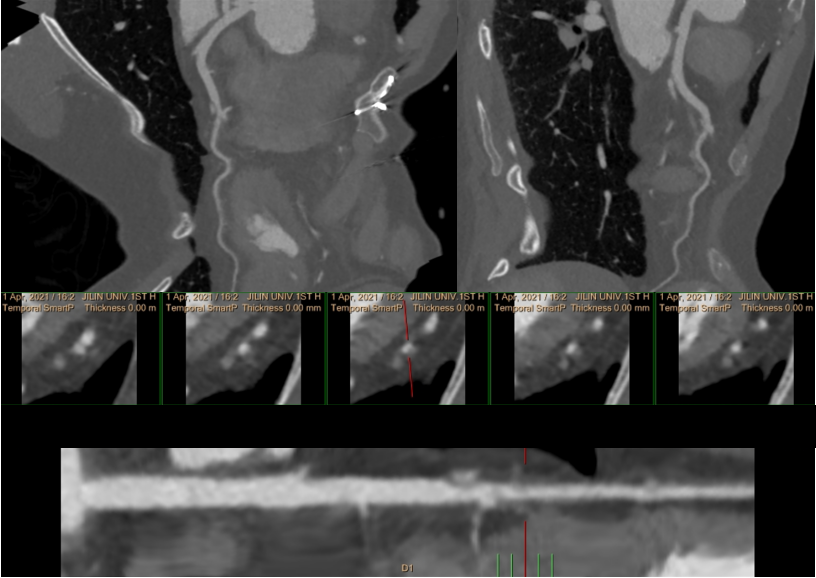

3、符合主动脉瓣及二尖瓣术后,请结合病史:男,64 岁,主因 「 突发胸痛 1 天 」。

左冠状动脉主干双腔影,诊断为夹层。

本例即为右冠状动脉近段 TYPE1 型,中段 TYPE2B 型;左冠状动脉前降支 TYPE1 型